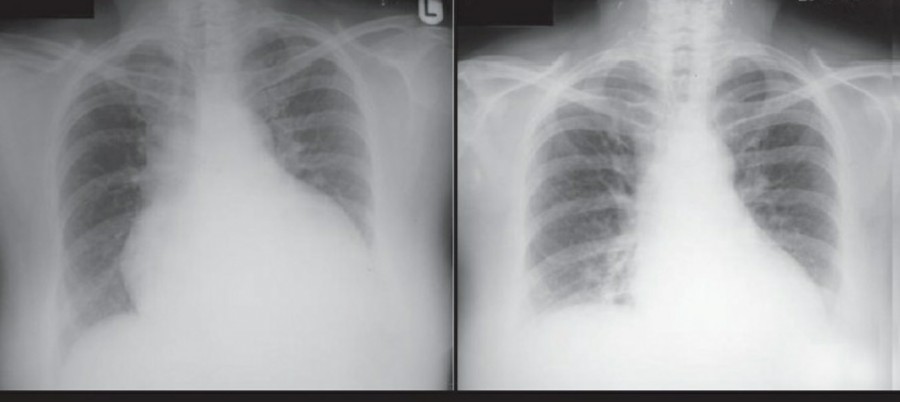

공기는 nondependent position으로 위치하므로, X ray상에서는 환자 자세에 따라 다르게 나타난다. Erect position에서 공기는 lung의 apicolateral surface에 위치하고 얇고 하얀 pleural line이 나타나며 그 뒤로 lung marking이 보이지 않는다.

하지만 pleural line 뒤로 lung marking이 존재한다고 해서 pneumothorax를 배제할 수 없다. Pneumothorax의 진단은 특히 parenchymal disease가 있을 때 진단하기 힘든데, 이는 compliance의 변화 때문에 collapse가 잘 안 되기 때문이다. Skin fold가 pneumothorax와 비슷하게 보이기도 한다.

중환자에서 pneumothorax의 진단은 종종 supine radiograph에서 내릴 수 있다. Supine position에서 공기는 anteromedial 방향으로 모이게 되는데, apical air collection이 있을 경우 large pneumothorax가 있음을 시사한다. 공기는 lung과 diaphragm 사이의 subpulmonic location에 trap 되어 있을 수도 있다. 공기가 costophrenic sulcus로 anterolateral extension 될 경우, 이 costophrenic sulcus의 radiolucency를 증가시키는데, 이를 deep sulcus sign이라고 한다. Subpulmonic pneumothorax의 다른 특징으로 diaphragm의 superior surface와 IVC 윗부분이 뚜렷하게 보일 수 있다.

중환자에서 tension pneumothorax의 진단은 매우 힘들다. ARDS와 같은 lung의 병리적인 기전이 lung compliance를 감소시킴으로써 total lumg collapse를 막는다. 또한 tension pneumothorax의 특징인 mediastinal shift가 PEEP으로 인해 나타나지 않을 수 있다. Chest X ray 상에서 tension pneumothorax는 hemidiaphragm의 depression이나 heart border, SVC, IVC의 이동으로 나타날 수 있다.